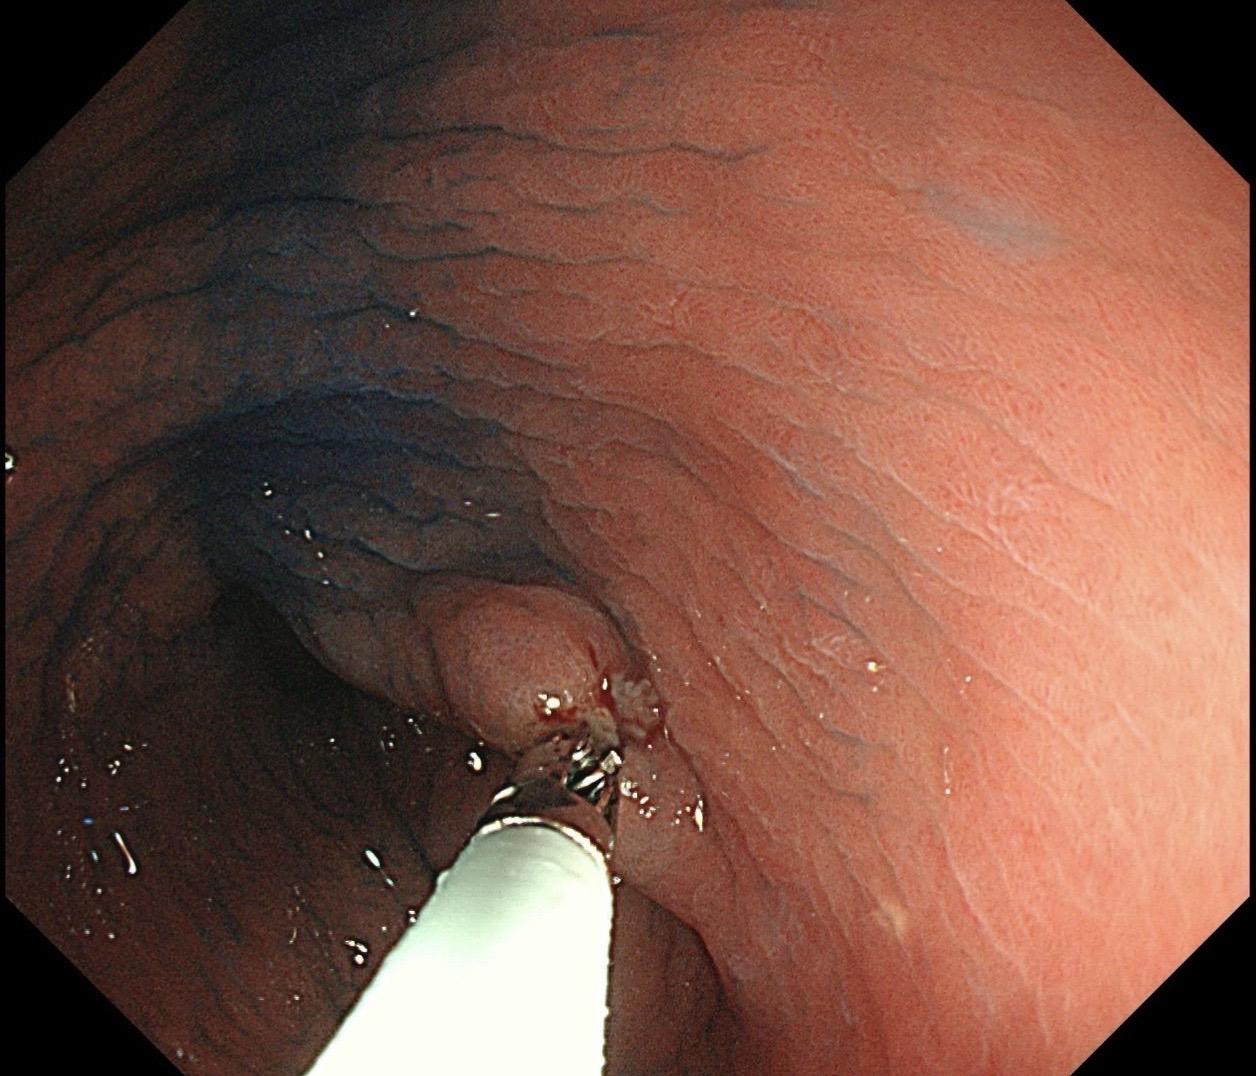

消化内镜王磊